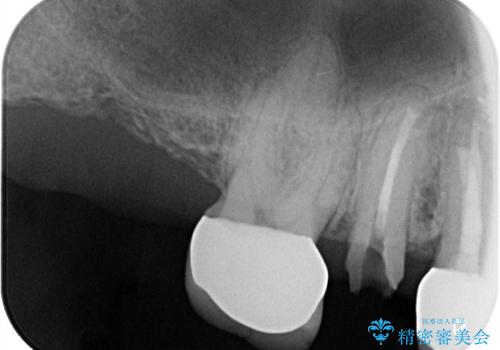

- 被せ物が外れたを主訴に来院された患者様です。

診査の結果保存困難だったので、抜歯後インプラント治療を行いました。